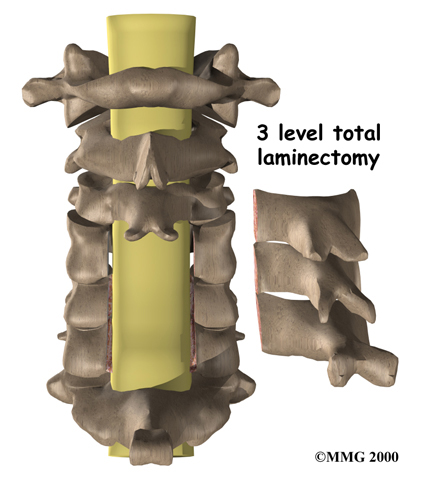

Laminectomy

The lamina is the covering layer of the bony ring of the spinal canal. It forms a roof-like structure over the back of the spinal cord.

When the nerves in the spinal canal are being squeezed by a herniated disc or from bone spurs pushing into the canal, a laminectomy removes part or all of the lamina to release pressure on the spinal cord.

Laminectomy

Related Document: FYZICAL Middleburg's Guide to Laminectomy